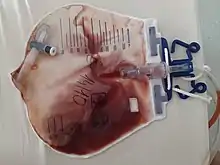

La mayoría de las hematurias proceden de la vejiga, especialmente en las mujeres y los ancianos. Debido a que la hematuria procedente de la vejiga puede conducir a la formación de coágulos eliminados durante la micción, la hematuria con coágulos orienta al diagnóstico de un sangrado vesical.

La cistitis es la causa de sangrado de la vejiga más frecuente, por lo general debido a la infección bacteriana, especialmente en las mujeres de todas las edades. Sin embargo, hay otras causas de cistitis, y entre las más importantes figura el síndrome de la cistitis intersticial, las causadas por drogas y la radiación. La hematuria por cistitis puede estar asociada a dolor y dificultad para orinar, frecuencia urinaria (que es la urgencia frecuente para orinar pequeños volúmenes de orina) y, a veces, la incontinencia urinaria. El diagnóstico es un examen de orina que permite el cultivo de un organismo y la terapia antibiótica específica.

Le sigue en frecuencia la presencia de neoplasias de la vejiga, pólipos o papiloma benignos o malignos. Su frecuencia aumenta con la edad y es mayor en los hombres. El diagnóstico es la ecografía vesical, seguida por lo general por una cistoscopia y también una biopsia, que permite un diagnóstico más definido del tipo de lesión.